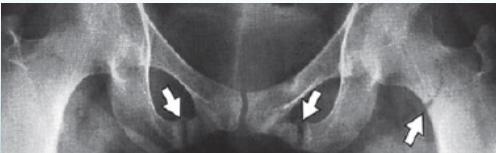

Characteristic Sign: Looser’s Zones

- Poorly healing stress fractures typically occurring at:

- Pubic bones

- Looser’s Zones (pseudo fractures). z

Looser’s zones Z are short lucent bands running through the cortex at right angles, usually going only part way across the bone